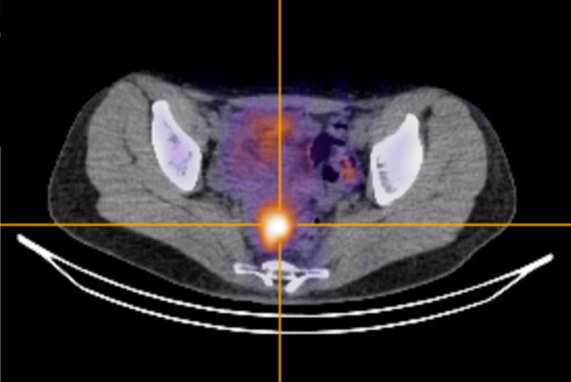

The Oxford facility and partner Serac Healthcare are investigating whether an imaging agent that uses the radioisotope technetium-99m maraciclatide to bind to areas of inflammation in the body can visualize endometriosis. The marker will be tested in a trial for women who will undergo imaging two to seven days before surgery for suspected endometriosis; the test findings will be compared with areas of disease found during surgery.